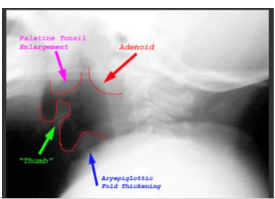

Epiglottitis on XRay

Careful positioning for x-rays

Lateral position is used

Not supine because airway occlusion could occur

Thumb Sign